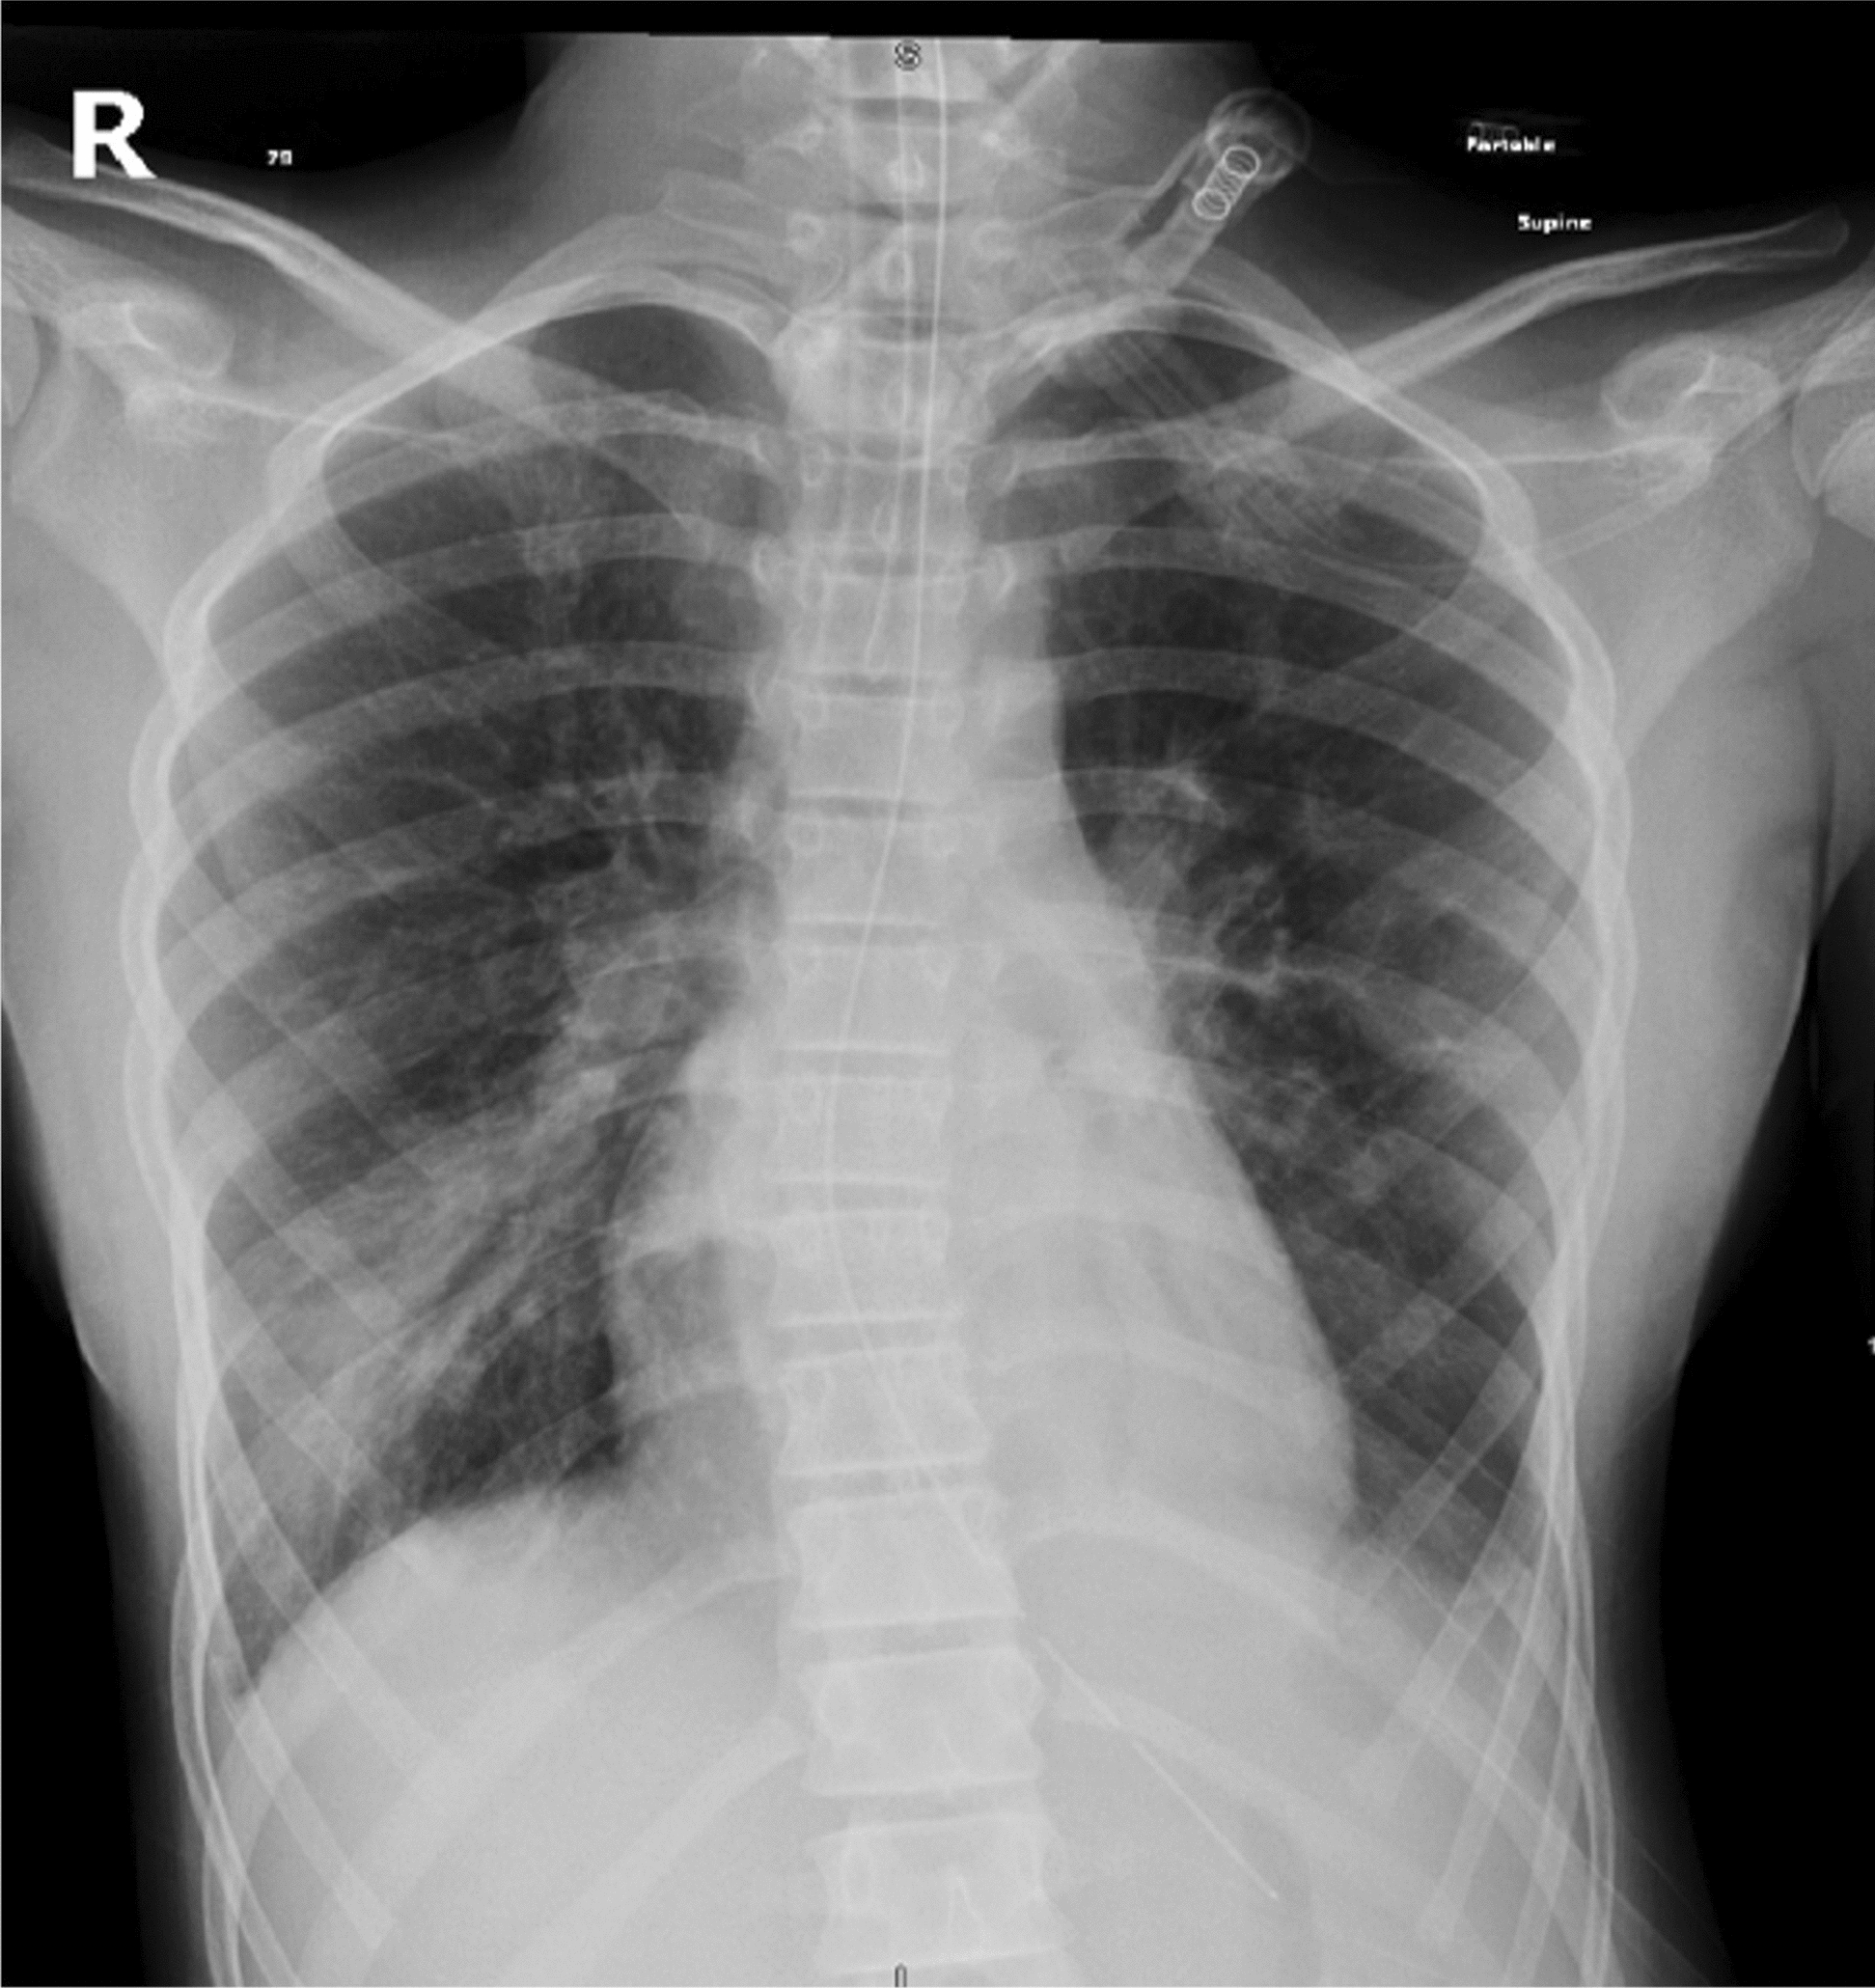

Case presentation: We report the case of a 12-year-old girl of Middle Eastern descent from Saudi Arabia with a history of bronchial asthma and allergic rhinitis who developed cerebral edema and resultant tonsillar herniation following a severe asthma exacerbation. Her presentation was marked by respiratory distress unresponsive to initial therapy. Intensive management in the pediatric intensive care unit including mechanical ventilation and neuroprotective measures resulted in full neurological recovery prior to discharge.